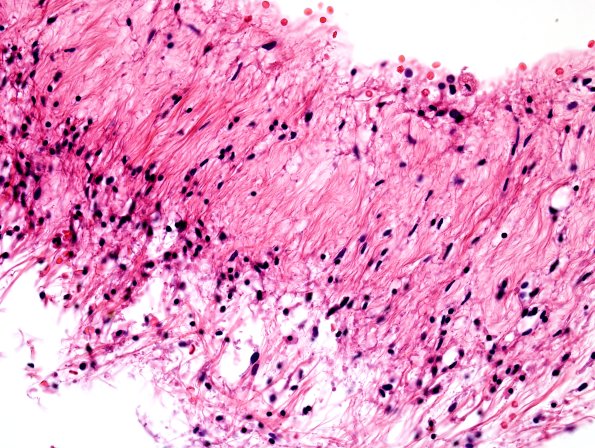

Higher magnification images of the residual brain tissue taken from the area marked with an arrow in image #11B1. (H&E)